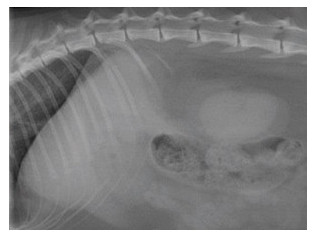

En plus de sensibiliser les propriétaires d’animaux à l’importance grandissante que prend l’imagerie vétérinaire dans le dépistage des pathologies et le maintien de la santé animale, la Journée internationale de l’imagerie vétérinaire nous a offert les résultats d’un vaste sondage réalisé en Belgique, en France et au Québec auprès de 894 médecins vétérinaires.

L’objectif de cette consultation était de découvrir l’opinion des vétérinaires généralistes sur la pertinence de faire appel aux spécialistes vétérinaires en imagerie médicale.Voici donc un résumé de ce premier grand sondage réalisé au sein de la francophonie vétérinaire qui démontre, au-delà des clichés, que malgré quelques différences de perception, l’état de la situation est sensiblement le même dans ces trois pays.